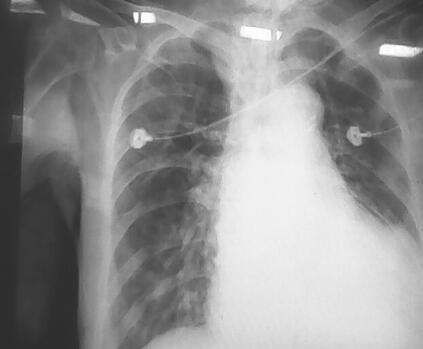

辅助检查:血气分析:pH 7.154,PCO2 38.7mmHg,PO2 88.3mmHg,COHb 27.8%,O2Hb 69.1%;电解质:钠147mmol/L,钾3.6mmol/L;血常规:WBC 18.71×109/L,N 89.24%,Hb 141g/L,PLT 177×109/L;D-二聚体896μg/L;生化指标:BUN 9.1mmol/L,Cr 88μmol/L,CK 178IU/L,CK-MB 14μg/L,Tn-i 1.52μg/L,BNP 14557.7pg/ml。心电图:房颤,ST-T改变;胸片:支气管炎,右下肺及左上肺炎症,右侧胸膜肥厚,心影增大(图1)。

图1 支气管炎,右下肺及左上肺炎症,右侧胸膜肥厚,心影增大